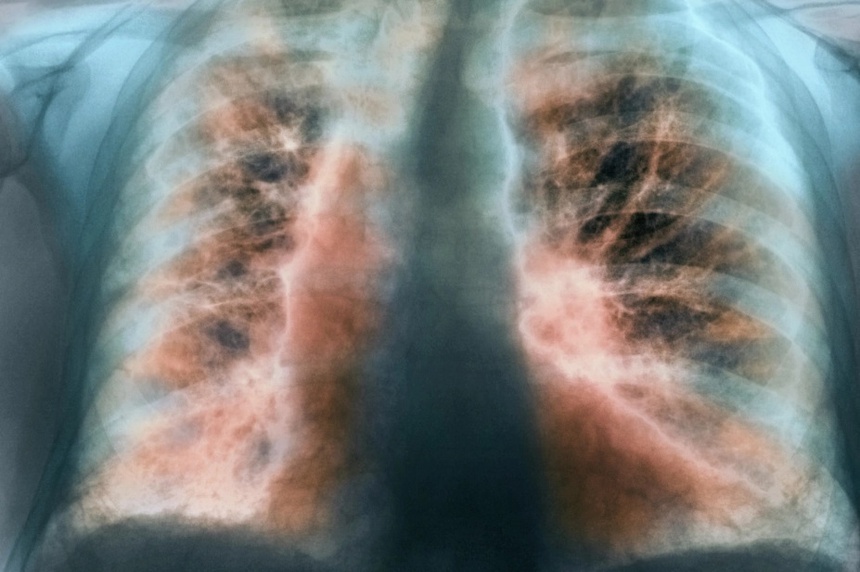

Hình ảnh tổn thương xơ hóa giai đoạn sớm và giảm chức năng phổi có thể xuất hiện ở mọi bệnh nhân bị viêm phổi do SARS-CoV-2.

Trên phim chụp CT scan ngực, hình ảnh xơ hóa phổi biểu hiện dưới nhiều dạng và mức độ khác nhau như dải xơ, dày các vách liên tiểu thùy, dạng lưới, giãn phế quản co kéo, phổi có hình tổ ong… Họ cũng có thể bị giảm thể tích phổi ở nhiều mức độ. Khi sinh thiết phổi, hình ảnh sẽ cho thấy tăng sinh tế bào tạo sợi và lắng đọng collagen trên mô bệnh học.